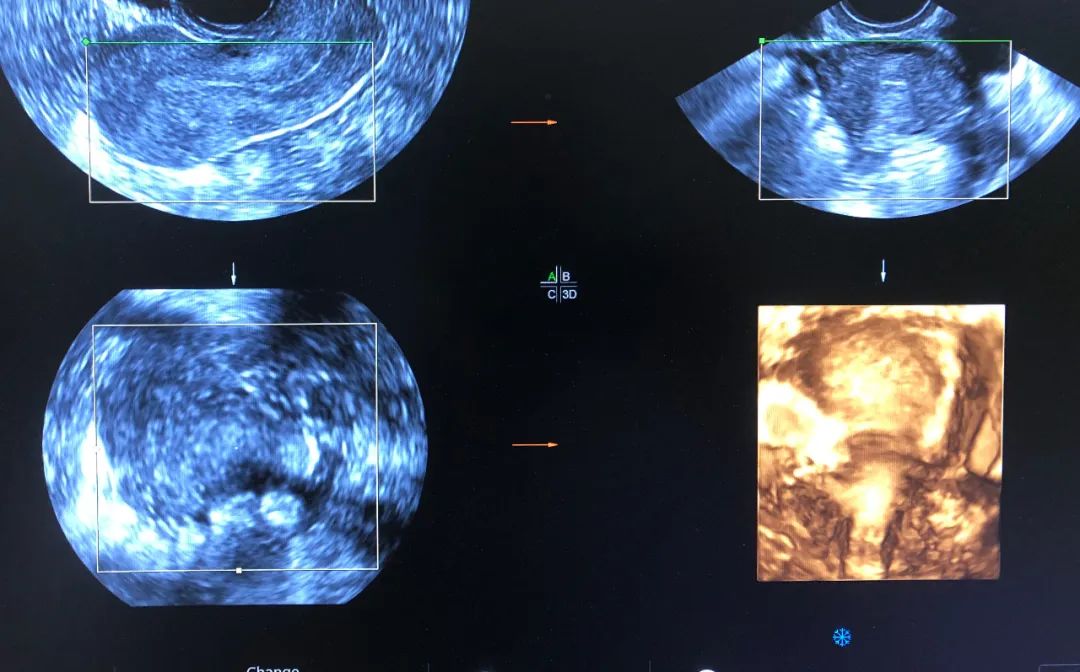

6月2日,一患者因外院超声诊断不全纵隔子宫来市妇幼院就诊,经常规妇科超声检查并未发现明显纵隔,与患者沟通后行经阴道四维超声检查,得到了清晰的图像诊断为弓形子宫,为妇科临床诊断提供了可靠依据。

腔内四维超声(4D-TVS)是在腔内二维超声基础上,利用计算机处理发展起来的新型超声诊断技术,可以提供更多的诊断信息,具有常规经阴道超声无法比拟的优势,立体直观,功能强大,可实现360度全方位无死角成像,大大弥补了单纯二维腔内超声的不够。

腔内四维超声检查可对先天性子宫畸形(完全或不完全纵隔子宫、弓状子宫、双角子宫、单角子宫、残角子宫等)、宫腔粘连、内膜息肉、粘膜下肌瘤进行诊断及鉴别诊断,还能清晰的视察到节育器的形态、位置,大大提高了超声在妇科疾病诊断中的准确率,为临床医生提供更准确的诊断信息,同时填补了我市在此项技术的空白。